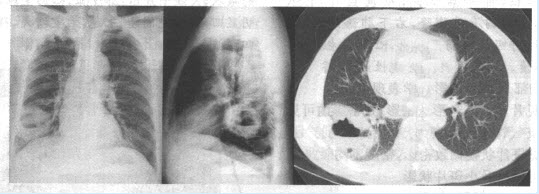

患者,男,45岁。受凉后寒战、高热1周,咳大量脓痰。X线平片如下图所示。

(单选题)最可能的诊断是()

A:肺脓肿

(单选题)诊断该病最可靠的X线征象为()

E:空洞内气液平面

(单选题)该病例空洞洞壁是由什么成分组成()

A:肉芽组织

E:肉芽组织十纤维组织